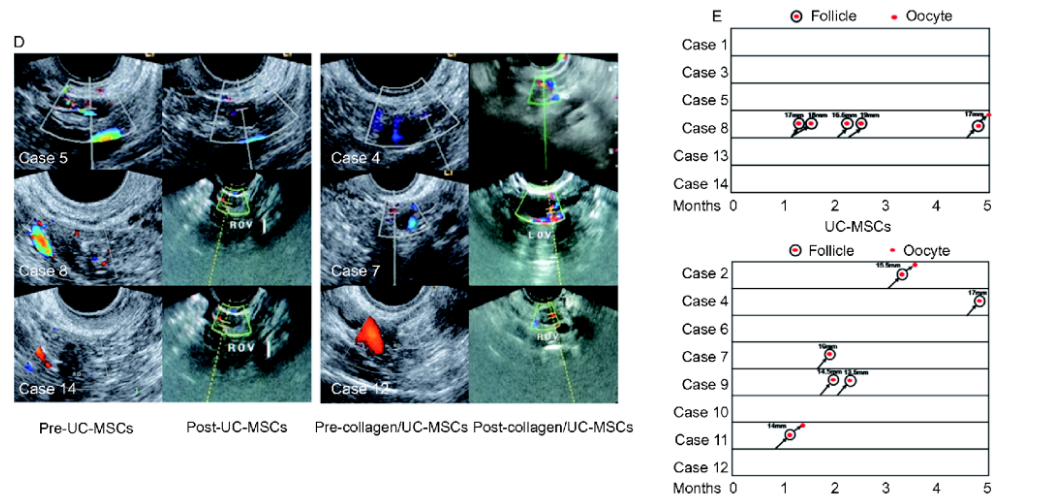

南京大学医学院附属鼓楼医院在脐带间充质干细胞复合胶原卵巢移植的方式治疗卵巢早衰所致的不孕症的研究结果表明:胶原/脐带间充质干细胞移植能够改善患者的卵泡活化和卵泡生长,并有助于卵巢功能的长期恢复,包括卵巢血流和雌二醇水平。而且,有2例患者在移植后成功受孕。

胶原/脐带间充质干细胞移植术后卵巢功能恢复